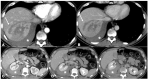

In industrialized countries, high energy trauma represents the leading cause of death and disability among people under 35 years of age. The two leading causes of mortality are neurological injuries and bleeding. Clinical evaluation is often unreliable in determining if, when and where injuries should be treated. Traditionally, surgery was the mainstay for assessment of injuries but advances in imaging techniques, particularly in computed tomography (CT), have contributed in progressively changing the classic clinical paradigm for major traumas, better defining the indications for surgery. Actually, the vast majority of traumas are now treated nonoperatively with a significant reduction in morbidity and mortality compared to the past. In this sense, another crucial point is the advent of interventional radiology (IR) in the treatment of vascular injuries after blunt trauma. IR enables the most effective nonoperative treatment of all vascular injuries. Indications for IR depend on the CT evidence of vascular injuries and, therefore, a robust CT protocol and the radiologist's expertise are crucial. Emergency and IR radiologists form an integral part of the trauma team and are crucial for tailored management of traumatic injuries.